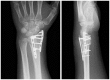

Background: The aim of this study was to compare the functional outcomes and complications of volar and dorsal plating for the management of intra-articular distal radius fractures, with special regard to indications for dorsal plating. Furthermore, we examine the rationale for choosing dorsal plating and its frequency of use.

Methods: Clinical assessments included range of motion measurements at the wrist; grip strength; the Quick Disabilities of the Arm, Shoulder, and Hand score; and the Gartland and Werley score. Clinical results were compared with those achieved using a volarly placed locking plate system. According to Lutsky's plate theory, the rationale for choosing dorsal plating was based on 4 types of pathologic fractures.

Results: Of 112 patients, 38 patients were treated with open reduction internal fixation via a dorsal approach and 68 patients were treated using a volar approach. Except for wrist flexion, there were no other statistical differences in the clinical results between groups for both subjective and objective parameters. There were no statistically significant differences in the complication rates between the volar and dorsal plated groups. One serious complication occurred after volar plating. The most common reason for choosing dorsal plating was irreducible dorsal die-punch fractures.

Conclusions: The treatment of displaced intra-articular distal radius fractures with a dorsally versus a volarly placed interlocking plate system demonstrated similar clinical results. Postoperative complications were not readily observed in the patients treated with a dorsal locking plate. Certain fracture patterns are more appropriately stabilized using a dorsal plate fixation.